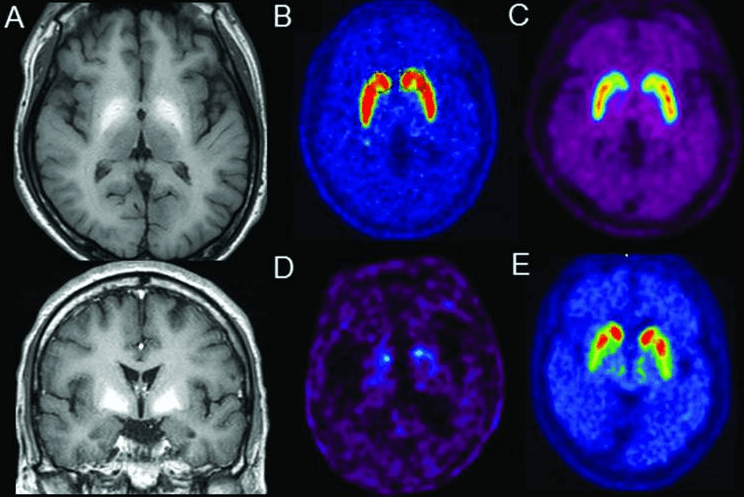

Independente do mecanismo, as neurotoxinas (amônia, manganês e outras) chegam ao cérebro, onde vão afetar principalmente os astrócitos, células responsáveis por manter e proteger os neurônios e auxiliar nas suas funções, incluindo retirar neurotransmissores usados das sinapses nervosas. No caso das hepatites fulminantes, os astrócitos incham e podem até causar hipertensão intracraniana intracraniana e óbito. Na cirrose e nas demais condições crônicas, esse inchaço é menos evidente ou não ocorre, surgindo alterações na célula chamadas de “astrócito de Alzheimer tipo II”. Não há ainda um consenso sobre o que exatamente acontece no cérebro, mas os astrócitos deixam de funcionar normalmente, o que causa um acúmulo de neurotransmissores. Além disso, a amônia, manganês, GABA e outras neurotoxinas pode agir como falsos neurotransmissores, estimulando ou inibindo neurônios ao acaso.

Transplante hepático

Assim como na maioria das complicações da cirrose, o transplante geralmente melhora os sintomas de encefalopatia hepática. Infelizmente, estudos mostram que parte dos danos causados pelas neurotoxinas são permanentes. Pacientes submetidos a transplante e que tiveram encefalopatia antes da cirurgia têm piora função cerebral do que os que não tiveram. Isso reforça a necessidade de diagnosticar e tratar a doença de forma mais agressiva e com medicamentos de uso contínuo, ao invés de apenas em crises, em pacientes que já tiveram algum sinal de encefalopatia.